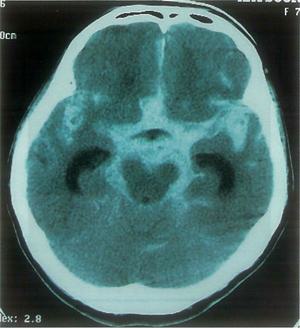

70歳の男性。頭部CTを示す。この患者の慢性期の症状で最も重度なのはどれか。

1

着衣失行

2

感覚障害

3

運動麻痺

4

不随意運動

5

半側空間無視

75歳の女性。突然の意識障害で搬入された。発症当日の頭部CTを示す。考えられるのはどれか。

脳塞栓

髄膜腫

脳内出血

硬膜下血腫

くも膜下出血

19

理学療法士実地問題 -

第44回 午前

重要度:重要

75歳の女性。突然の意識障害で搬入された。発症当日の頭部CTを示す。発症3日目のJCS(Japan coma scale)は10点であった。この時点での理学療法で適切なのはどれか。2つ選べ。

体位変換

座位訓練

移乗訓練

腹筋強化

関節可動域訓練